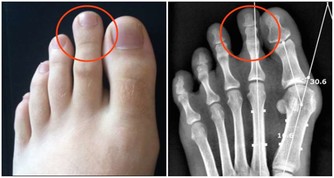

3、痔瘡也是因為缺乏維生素B2引起的。

輕微缺乏維生素B2人體不會有任何感覺,但到一定程度時就會出現明顯的症狀,首先,在人體最薄弱的地方,通常是消化道的首尾兩端,即口腔或肛門的局部,出現充血、腫脹,隨後皮膚或粘膜出現潰瘍,然後開始出血,這即是口腔潰瘍和痔瘡。如果長期缺乏維生素B2,那麼人體其它部位也會出現同樣的症狀。

主要原因在於血管,構成血管壁的細胞離不開維生素B2,當缺乏維生素B2時,血管壁(主要是毛細血管,管壁本身就很薄)開始變薄,在血壓的作用下,血管開始向外凸起,當局部的血管都開始鼓起時,就形成了腫塊,最後血管開始裂開出血,如果發生在腦部,你猜到了嗎?對,這就是腦溢血。